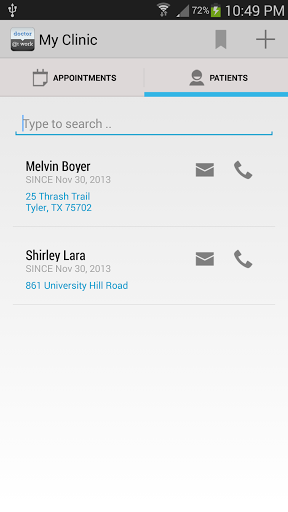

• Obtenir des informations patient directement à partir de vos contacts téléphoniques

• Envoyer un rappel de rendez-vous médical au patient par courriel ou par SMS

• Envoyer le résumé de la visite au patient par email ou SMS

• Personnalisez les informations patient que vous souhaitez capturer